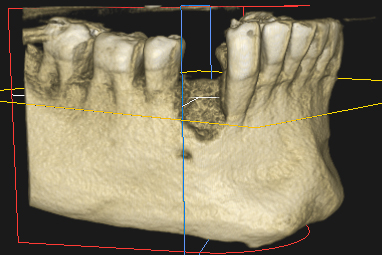

Injerto de hueso dental

Un injerto de hueso dental es un procedimiento quirúrgico que estimula la regeneración de la masa ósea que da soporte al implante. Se hace por medio de materiales biológicos o sintéticos.

Un injerto de hueso dental es una técnica quirúrgica que permite aumentar la masa ósea en el maxilar o la mandíbula.

Mediante la implantación de material de injerto se promueve la regeneración de las células óseas con el fin de aumentar su volumen y restaurar tanto su capacidad de soporte como su estética.

Este tratamiento puede tener diferentes finalidades. La más habitual es proporcionar el soporte necesario para la colocación de implantes.